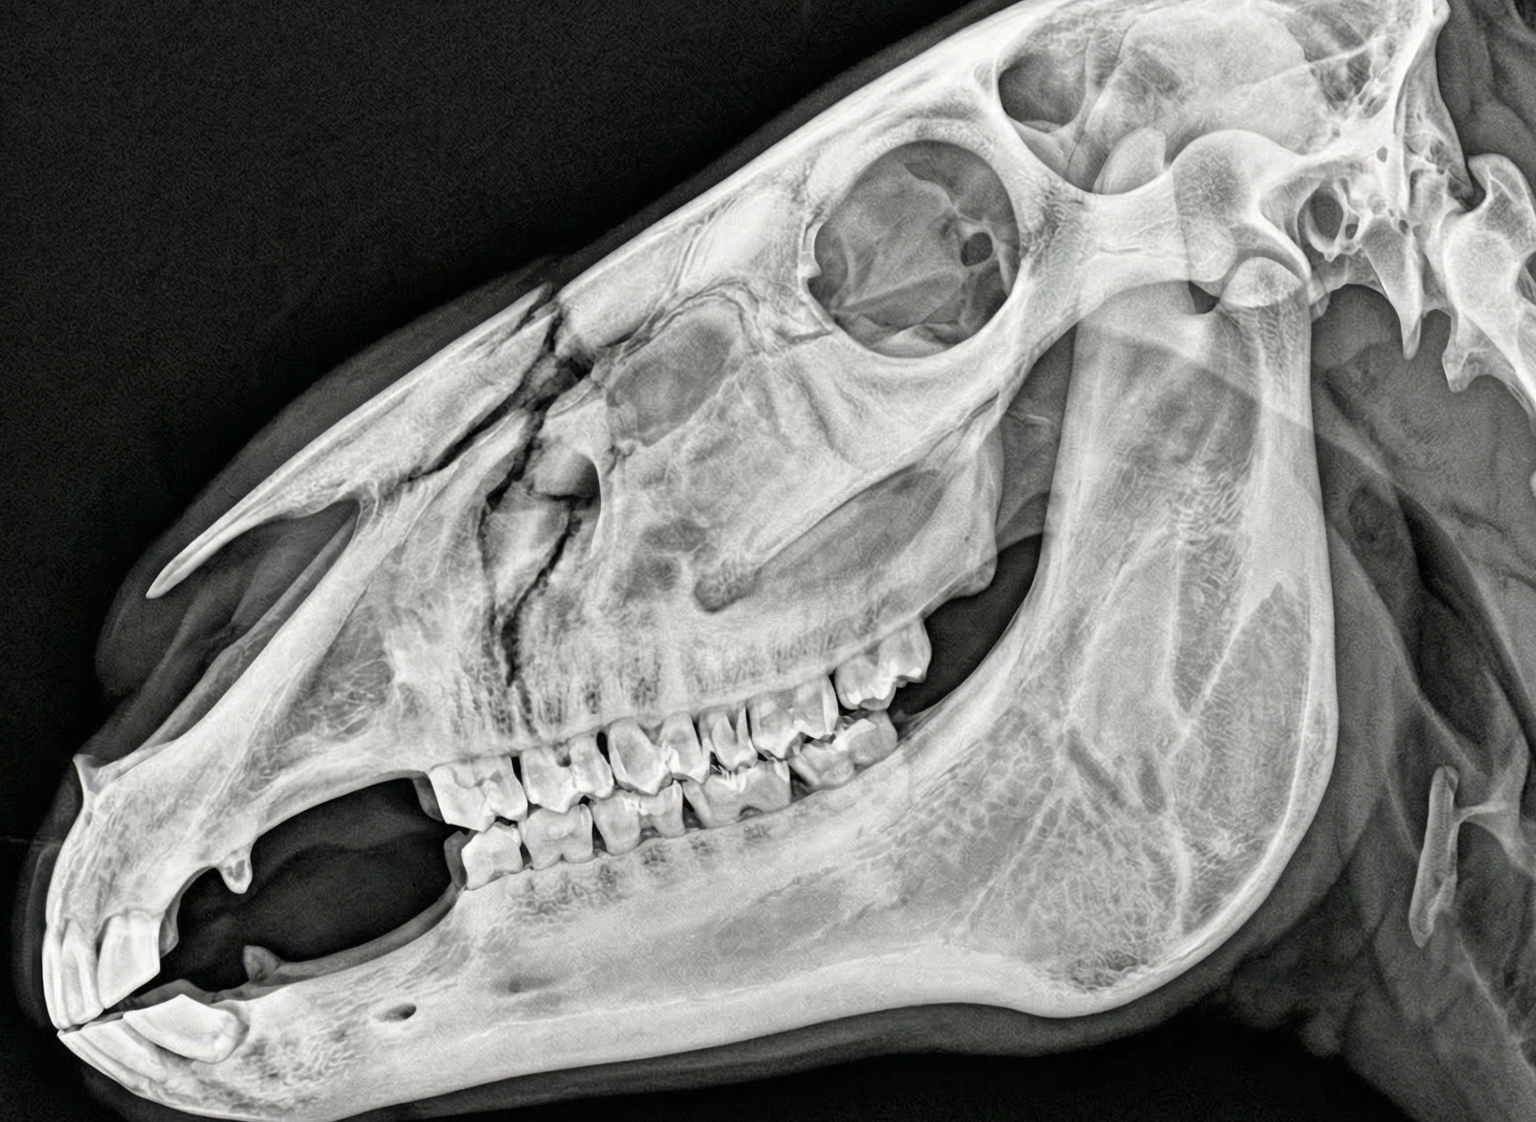

Tierart wählen

Hund, Katze, Pferd, Rind oder Exoten. Region: Thorax, Abdomen, Extremitäten, Schädel.

Animioo erkennt über 80 Befundmuster — von der Lobärpneumonie beim Hund bis zum Hufgelenk-Arthrosegrad beim Pferd.